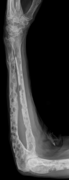

The diagnostic examination of a person with suspected multiple myeloma typically includes a skeletal survey. This is a series of X-rays of the skull, axial skeleton, and proximal long bones. Myeloma activity sometimes appears as "lytic lesions" (with local disappearance of normal bone due to resorption) or as "punched-out lesions" on the skull X-ray ("raindrop skull"). Lesions may also be sclerotic, which is seen as radiodense.[70] Overall, the radiodensity of myeloma is between −30 and 120 Hounsfield units (HU).[71] Magnetic resonance imaging is more sensitive than simple X-rays in the detection of lytic lesions, and may supersede a skeletal survey, especially when vertebral disease is suspected. Occasionally, a CT scan is performed to measure the size of soft-tissue plasmacytomas. Nuclear Medicine Bone scans are typically not of any additional value in the workup of people with myeloma (no new bone formation; lytic lesions not well visualized on nuclear bone scan).

X-ray of the forearm, with lytic lesions